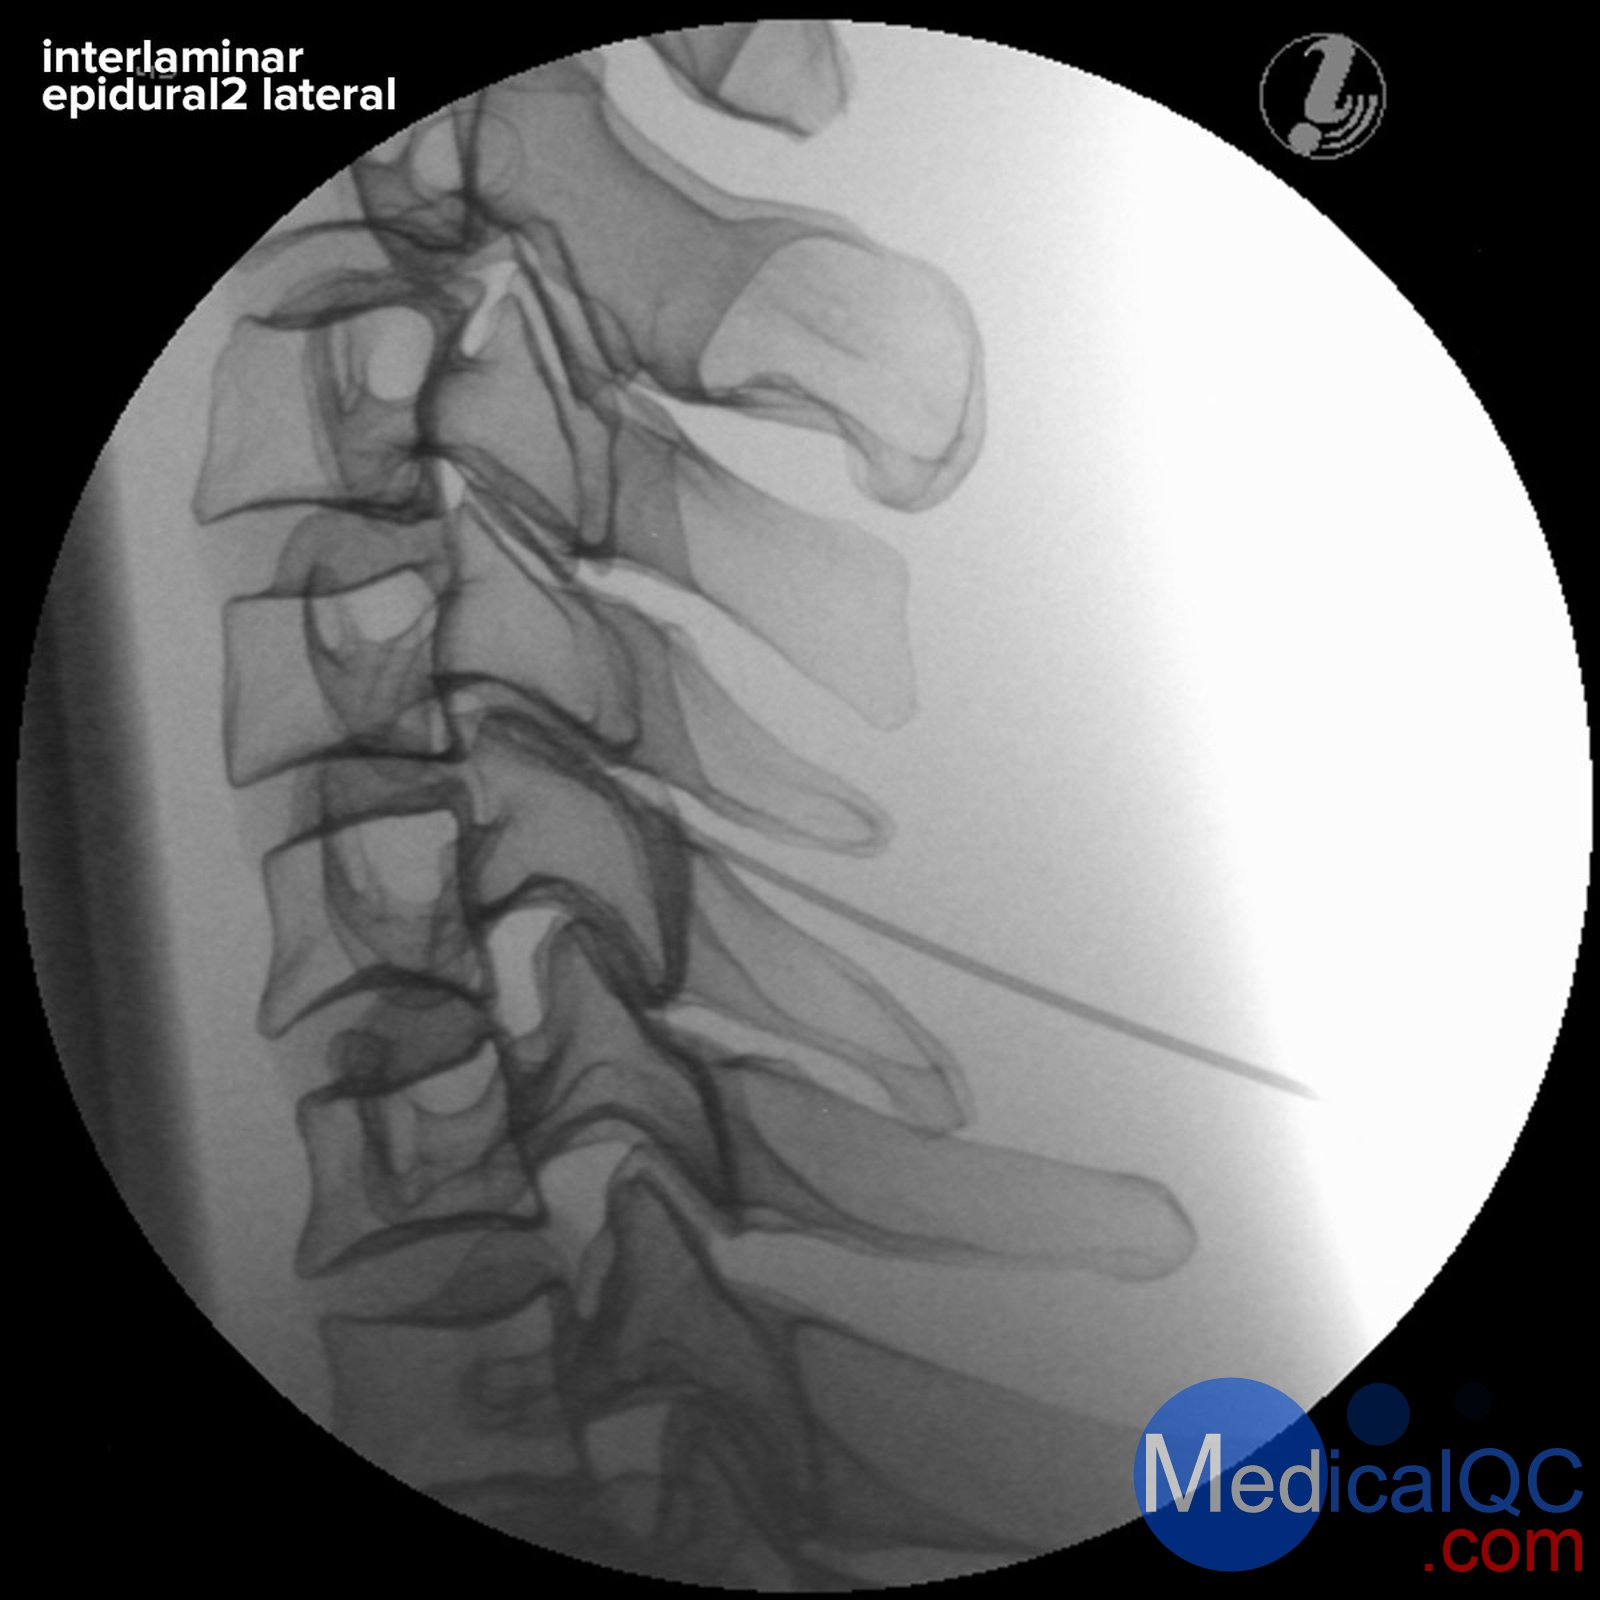

3B P67頸椎圖像引導(dǎo)穿刺訓(xùn)練模體,3B P67頸椎穿刺訓(xùn)練模體支持圖像的頸椎注射訓(xùn)練器

3B P67頸椎圖像引導(dǎo)穿刺訓(xùn)練模體,3B P67頸椎穿刺訓(xùn)練模體對(duì)頸椎栩栩如生的射線不透逼真的圖像引導(dǎo)下注射訓(xùn)練

圖像引導(dǎo)宮頸注射教練讓學(xué)員開發(fā)成功的脊柱手術(shù)過程的立體的認(rèn)識(shí)。他們將學(xué)習(xí)如何通過成像和解剖學(xué)檢查將成像與頸椎解剖結(jié)構(gòu)相關(guān)聯(lián),以識(shí)別目標(biāo)組織和脆弱結(jié)構(gòu),并應(yīng)用最佳實(shí)踐以確?;颊咴诩怪中g(shù)期間的安全性。

3B P67頸椎圖像引導(dǎo)穿刺訓(xùn)練模體,3B P67頸椎穿刺訓(xùn)練模體采用渦流噴射教練是成像尸體上的課程和BioSkills實(shí)驗(yàn)室經(jīng)濟(jì)的選擇,并提供教練的可靠,標(biāo)準(zhǔn)化病人的模擬是隨時(shí)使用:

逼真的X射線圖像具有逼真的射線不透性

現(xiàn)實(shí)注射觸覺

解剖學(xué)上準(zhǔn)確的骨骼結(jié)構(gòu)

可見和觸覺的地標(biāo)

3B P67頸椎圖像引導(dǎo)穿刺訓(xùn)練模體,3B P67頸椎穿刺訓(xùn)練模體可以在模擬器上訓(xùn)練以下基于圖像的脊柱干預(yù):

基于地標(biāo)的干預(yù)技術(shù)

封鎖內(nèi)側(cè)分支

枕骨阻塞

小關(guān)節(jié)的高頻去神經(jīng)支配

關(guān)節(jié)內(nèi)C1 / C2

關(guān)節(jié)內(nèi)頸椎/小關(guān)節(jié)

Interlaminar硬膜外注射

3B P67頸椎圖像引導(dǎo)穿刺訓(xùn)練模體,3B P67頸椎穿刺訓(xùn)練模體顯示以下骨骼結(jié)構(gòu):

枕骨(顱骨到枕骨突起)

椎骨C1-Th2

肋骨1和2